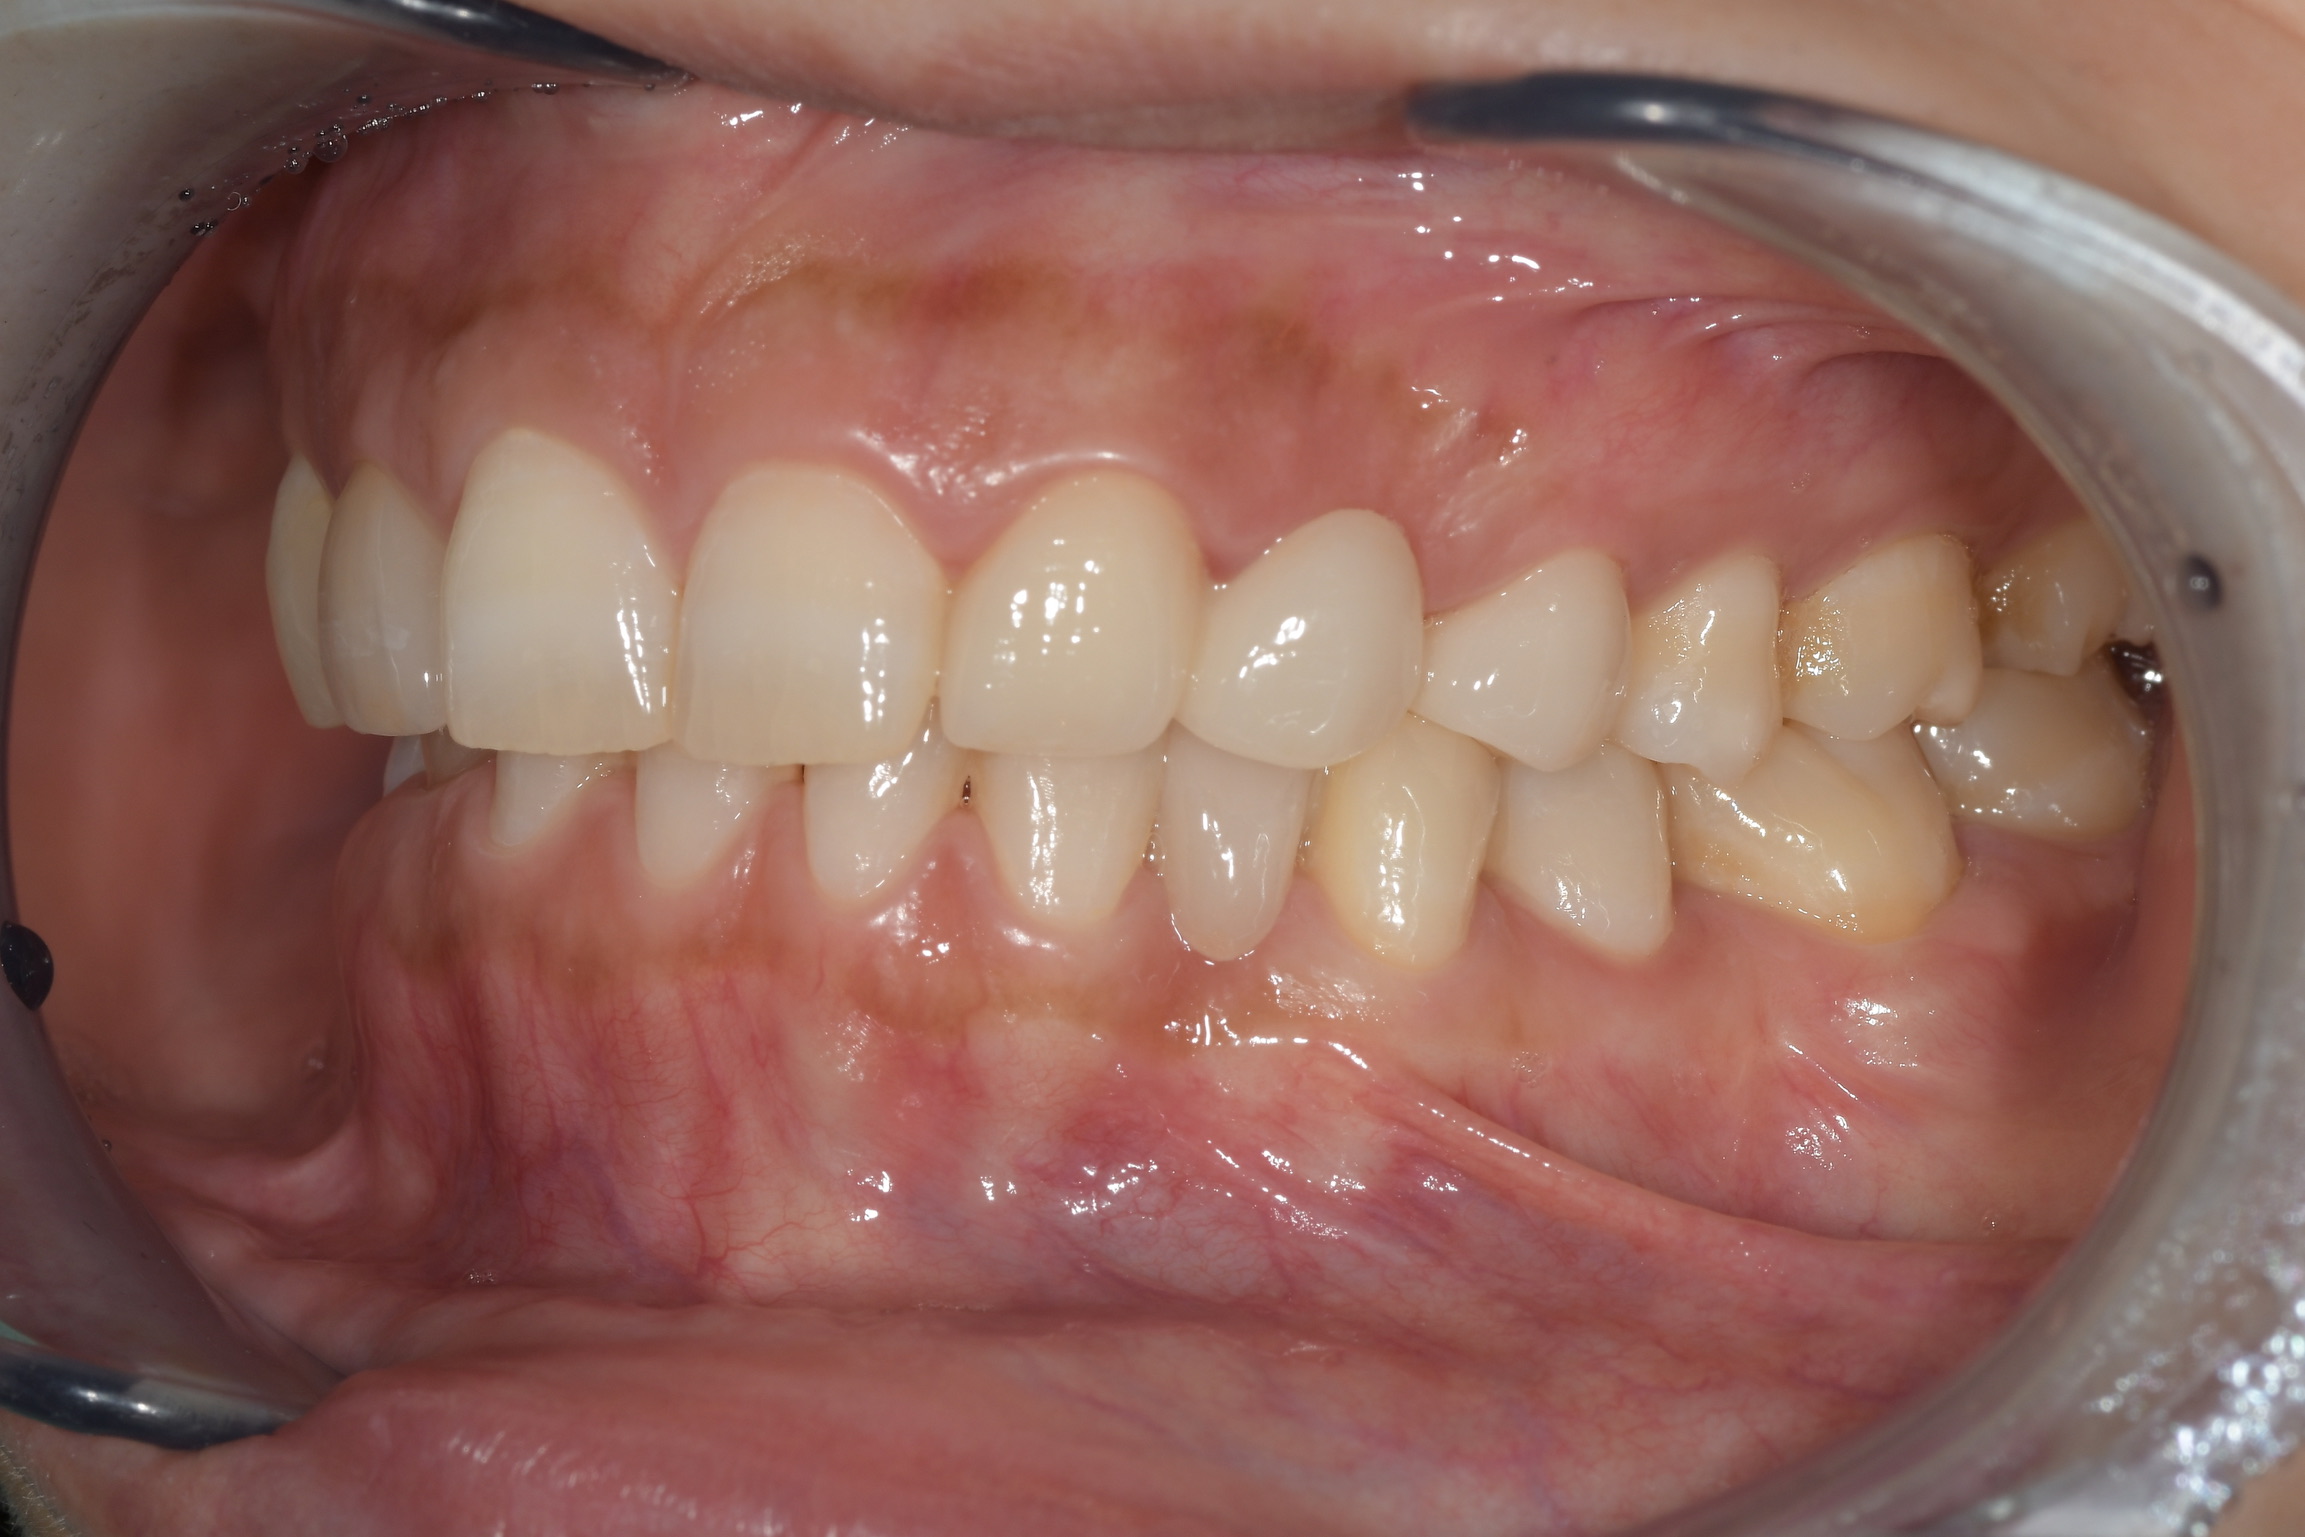

別の例として

同じ患者さんで保険診療の金属接着ブリッジと、自由診療のセラミック接着ブリッジをお口の中に入れて比較した写真ですが

比べてみると保険の金属接着ブリッジは金属が見えたり、透明感のない歯になっています。

セラミック接着ブリッジは金属が見えないのと透明感のある歯になります。